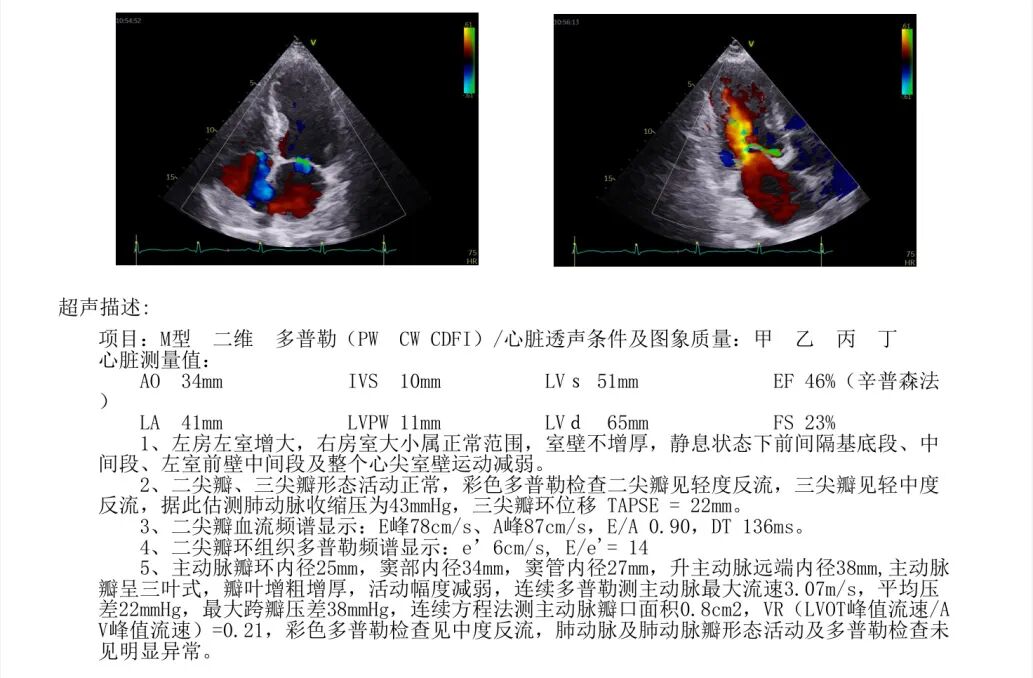

进一步检查显示,患者存在主动脉瓣重度狭窄并中度反流。超声心动图提示,主动脉瓣口面积约0.8cm²,同时伴有室壁节段性运动异常、左房及左室增大,左室收缩和舒张功能减退,左室射血分数为46%。此外,还可见二尖瓣轻度反流、三尖瓣轻至中度反流及轻度肺动脉高压。

患者为男性,82岁,近两年来反复出现头晕不适,并曾发生多次晕厥;近两个月来又间断出现胸闷不适,多在体力活动时发作,休息后可缓解。此次到院检查发现,NT-proBNP升高,心超提示主动脉瓣重度狭窄合并轻中度反流。

▲患者心超

术后复查显示,患者瓣膜功能改善明显,最大跨瓣压差较术前明显下降,峰值流速同步改善。术后第3天,患者已可在家属搀扶下下地活动,胸闷、头晕等症状较前缓解,随后顺利出院。